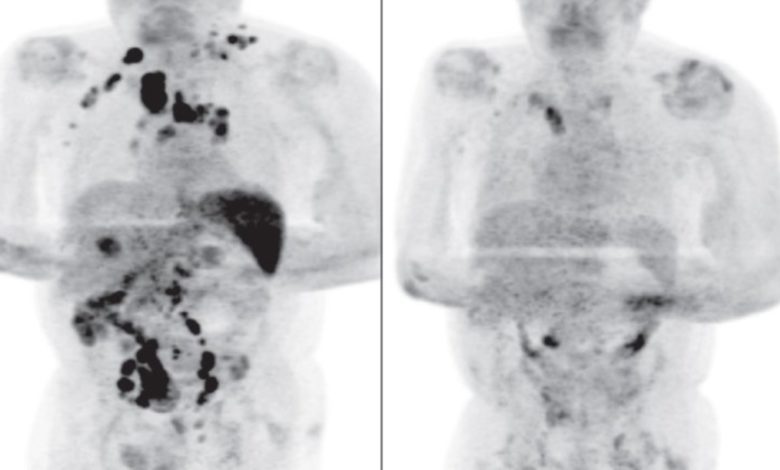

Investigan a paciente que se curó de cáncer tras contagiarse de COVID-19

Durante la pandemia del COVID-19 se han presentado múltiples casos que han sorprendido a doctores y expertos; sin embargo, el de un hombre de 61 años dejó atónitos a todos al curarse de cáncer...